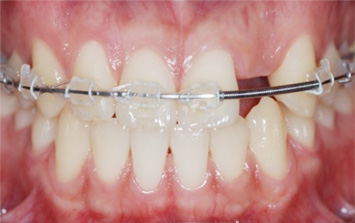

오른쪽 앞니 상실로 내원한 환자분. 앞니의 상실로 치아 사이 틈이 넓어지고 있어 교정으로 임플란트 식립 공간을 만든 후

임플란트 식립을 하였습니다. 앞니가 상실된 기간이 길어 교정치료를 하지 않고 임플란트를 식립할 경우

벌어진 치아 사이로 음식물이 끼거나 치아형태 이상으로 문제가 생길 수 있습니다.